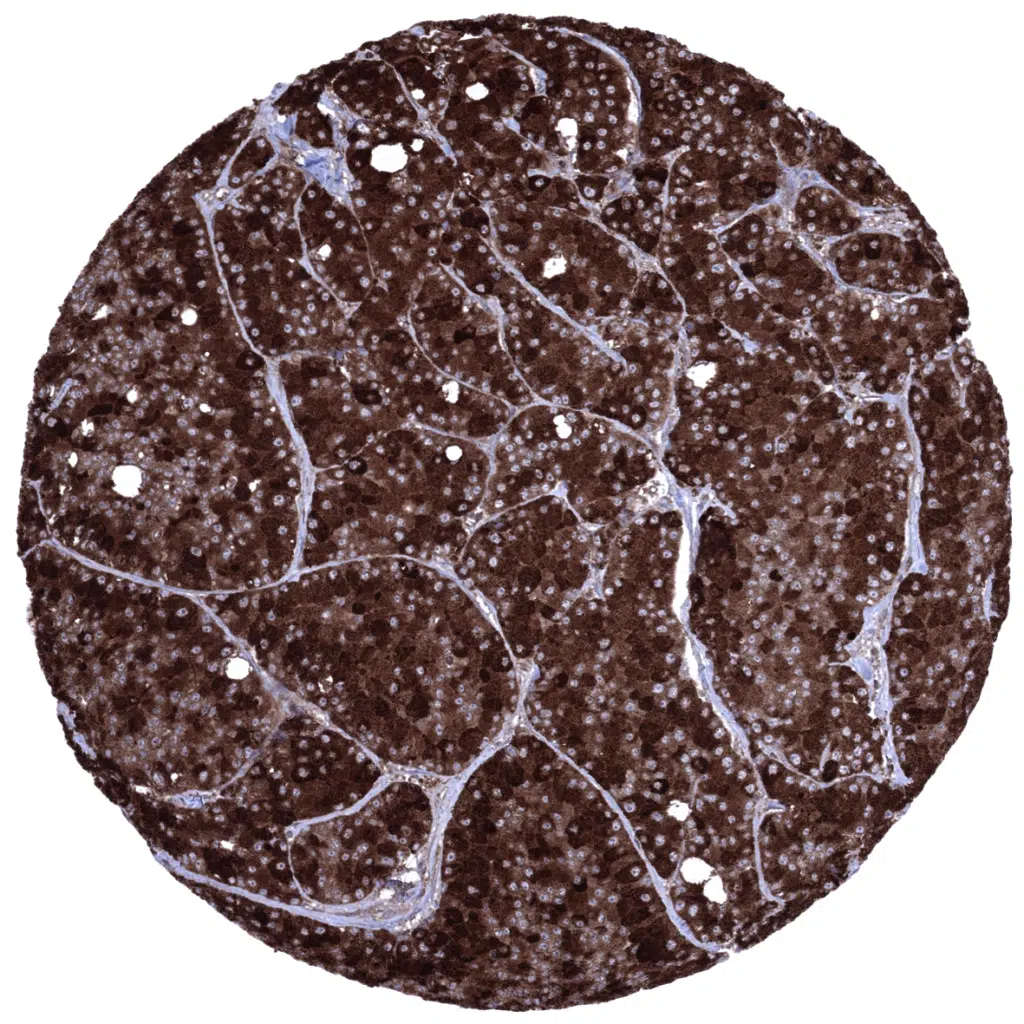

Pancreas - Acinar cell carcinoma showing strong Elastase 3B immunostaining of all tumor cells.